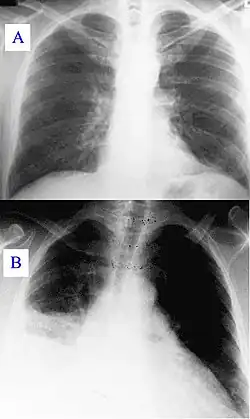

| A) Normal chest radiograph; B) Q fever pneumonia affecting the right lower and middle lobes. Note the loss of the normal radiographic silhouette (contour) between the affected lung and its right heart border as well as between the affected lung and its right diaphragm border. This phenomenon is called the silhouette sign | |

In radiology, the silhouette sign refers to the loss of normal borders between thoracic structures.[1] It is usually caused by an intrathoracic radiopaque mass that touches the border of the heart or aorta.[2] In other words, it is difficult to make out the borders of a particular structure - normal or otherwise - because it is next to another dense structure, both of which will appear white on a standard X-ray.[3] It may occur, for example, in right middle lobe syndrome, where the right heart margin is obscured, and in right lower lobe pneumonia, where the border of the diaphragm on the right side is obscured, while the right heart margin remains distinct.[2] Silhouette sign is very useful in localizing lung lesions as all structures forming cardiac silhouette are in contact with a specific portion of the lung.